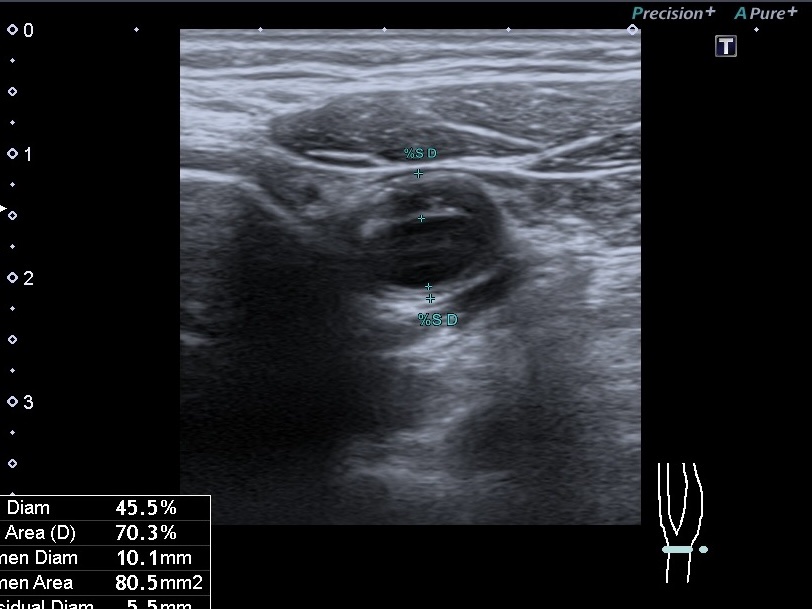

Різниця між 2 та 3 категоріями полягає в товщині стінки: якщо максимальна товщина стінки в місці бляшки до 3 мм — це 2 тип, якщо більше 3 мм — 3 тип. 2 категорія АСБ вважається категорією з низьким ризиком інсультів.

Порада від лікаря: Знати тільки відсоток стенозу (звуження) судини — недостатньо. Важливо розуміти “якість” бляшки. Навіть невелика, але нестабільна бляшка може бути небезпечнішою за велику стабільну.